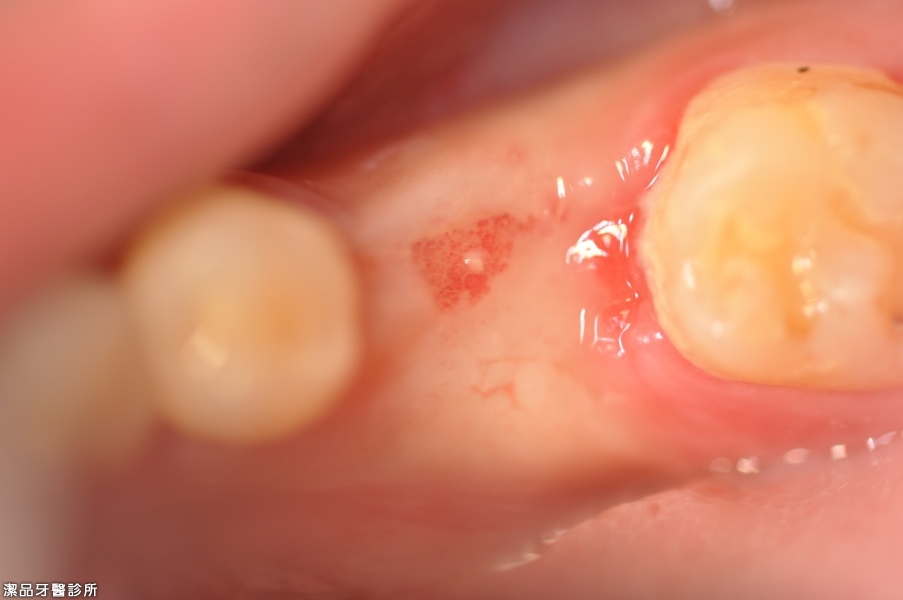

拔牙+補骨後4個月恢復狀況良好已有足夠骨頭植牙